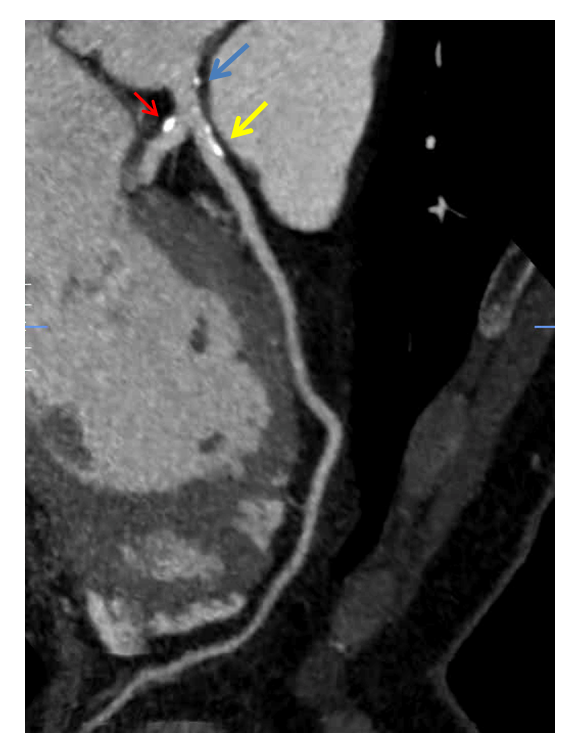

A coronary CT angiogram is ordered which showed a left dominant system and evidence of non-obstructive plaque (figures I-III). Coronary calcium score is 189, which is > 95th percentile for age/gender/race (see table 1). Her Segment Involvement Score (SIS) is 3, Segment Stenosis Score (SSS) is 0 and CT-Leaman Score (CT-LeSc) is 9 Smoking cessation is recommended.

Figure I: Coronary CTA showing LAD with calcified plaque (yellow arrow). Plaque in LCX (red arrow) and LM (blue arrow) can also be seen

Figure II: Coronary CTA showing calcification in the proximal circumflex artery